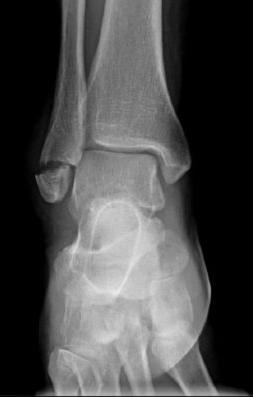

What is it?

A Weber A ankle fracture is a break at the tip of fibula, the smaller of the two bones in the lower leg. This type of fracture is considered stable and often heals well without the need for surgery.